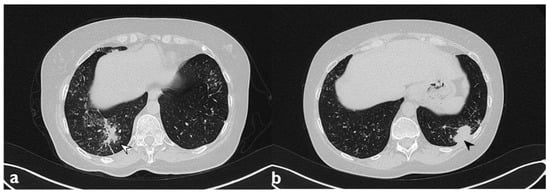

Figure 2. Typical pattern: multifocal and asymmetrical parenchymal consolidations (arrowheads), with peripheral distribution. These lesions may reproduce an air bronchogram sign in the context.

The classical form of COP is characterized by multifocal parenchymal consolidations, often bilateral and asymmetrical. These findings are usually described as patchy or with peripherical or peribronchial predominance in lower lobes. They tend to migrate, disappearing spontaneously and appearing in different sites (Figure 2) [22,26]. Consolidations may be associated with GGOs; usually, these lesions may reproduce an air bronchogram sign in the context [22]. At the moment of the onset, this typical pattern has been encountered in about 75% of patients [22,24,25,26].